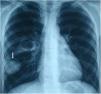

A 17 years old male presented with cough. Posteroanterior and lateraly direct radiography showed cavitary lesion in the middle zone and “moonsign” in the lower zone of the right lung (Figs. 1 and 2). The patient underwent right thoracotomy. Cystotomy and capitonnage was performed to hydatid cyst.

Fig. 2.

Moon sign is seen on the lateral chest X-ray (arrow).

Radiologically, there are many radiological signs associated with the hydatid cyst.1,2 Moon sign is seen when air enters between the pericyst and endocyst. This finding indicates that the hydatid cyst will rupture. Radiological findings have an important role in the diagnosis of pulmonary hydatid cyst.